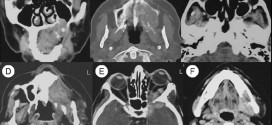

CARCINOMA EPIDERMOIDE DE OÍDO MEDIO

El carcinoma epidermoide de oído medio. Los carcinomas epidermoide de oído medio son raros 1-2/1000000/año. CAE/oído medio: 10/1. Tipo histológico más frecuente Ca epidermoide (70%), seguido del Ca basocelular. Durante los primeros años de vida de una persona, las células normales se dividen más rápidamente para permitir el crecimiento. El cuerpo está compuesto por billones de células vivas. Las células …